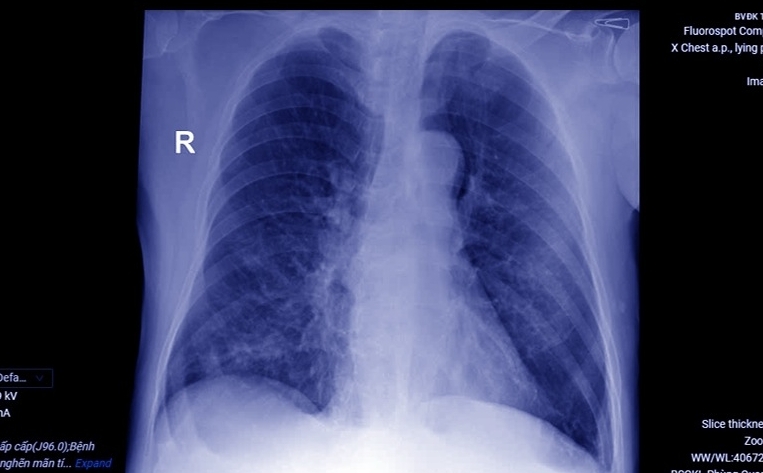

Hình ảnh phổi tổn thương do bệnh chuyển biến nặng. (Ảnh: BV)